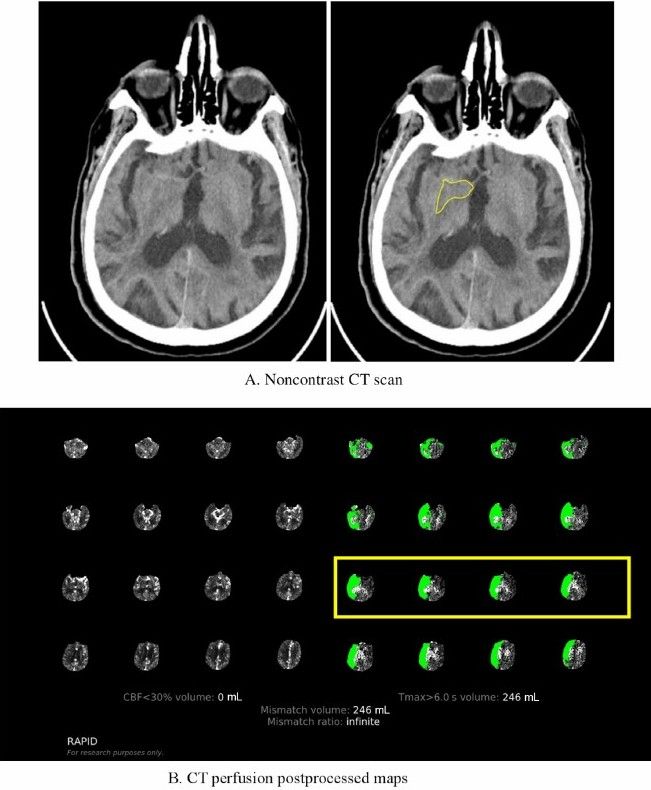

onlinelibrary.wiley.com/doi/epdf/10....

#neuroimaging #neurology #neuroskyence #radiology #stroke #perfusion #mri

Free read

onlinelibrary.wiley.com/doi/epdf/10....

#neuroimaging #neurology #neuroskyence #radiology #stroke #perfusion #mri

Free read

onlinelibrary.wiley.com/doi/epdf/10....

#neuroimaging #neurology #neuroskyence #radiology #stroke #ghostpenumbra

onlinelibrary.wiley.com/doi/epdf/10....

#neuroimaging #neurology #neuroskyence #radiology #stroke #ghostpenumbra